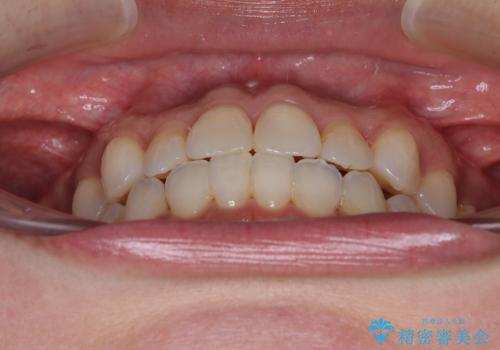

前歯のクロスバイト インビザラインによる矯正治療

- 上下のクロスバイトと前歯のデコボコを気にして来院された患者様です。

インビザラインを用い、IPR(歯と歯の間を削る)と歯列全体を拡大させることで、歯並びを整えていくこととしました。